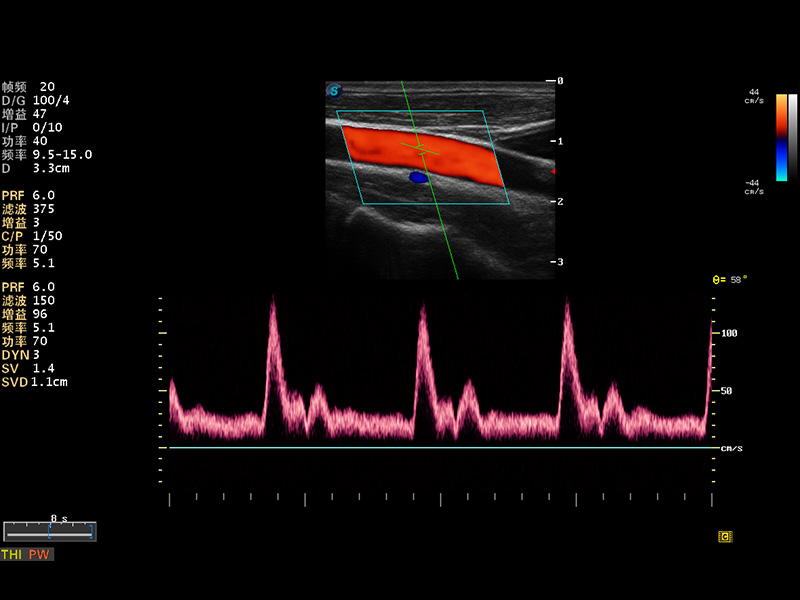

S8 EXP便携式彩色多普勒超声诊断仪是球速体育入口研发的高端全身应用型便携彩超。高通道的VIS平台融合可视化(Visual)、智能化(Intelligent)和人性化(Smart)的特点,配以球速体育入口自主研发生产的探头大家族,使您能够快速、准确的获得病人信息,提高工作效率的同时减轻疲劳。

多波束形成器

μ-Scan微米成像